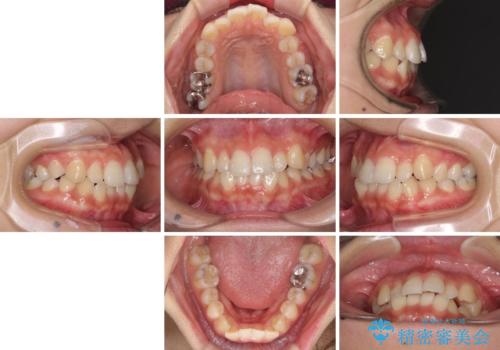

前歯の突出感とデコボコ インビザラインで改善

- 上下前歯のデコボコを気にして来院された患者様です。

インビザラインによる上下歯列の側方拡大と後方移動、IPR(歯と歯の間を削る)にるスペースの獲得により歯列を整えることとしました。

右上の小臼歯は歯根癒着をしており、様々な方法を試みるも動かすことができませんでした。

それでも奥歯のかみ合わせに不自由はなく、歯列をきれいに整えることができました。